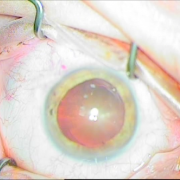

H επιστημονική μας ομάδα έχει την ικανότητα αντιμετώπισης όλων των τύπων των καταρρακτών, απλών, με μικρή κόρη, υπερώριμων, με φακοδόνηση, μετά από Laser μυωπίας και υπερμετρωπίας, καθώς και σοβαρότερων επιλεγμένων περιπτώσεων.

Διαθέτουμε την εμπειρία για χρήση ειδικών τύπων ενδοφακών, όπως είναι οι αστιγματικοί οι πολυεστιακοί, οι ιριδικής στήριξης και πολλών άλλων. Όλα αυτά συμβάλλουν στην αντιμετώπιση του καταρράκτη με ποιοτικό και εξατομικευμένο τρόπο.

Οι σύγχρονες μικροχειρουργικές τεχνικές αποβλέπουν στον ελάχιστο τραυματισμό του οφθαλμού και στην τοποθέτηση του τεχνητού ενδοφακού στην φυσική του θέση που είναι ο οπίσθιος θάλαμος. Οι ασθενείς απολαμβάνουν τα πλεονεκτήματα των επεμβάσεων μικρής τομής χωρίς ράμματα, με άμεση αποκατάσταση της όρασης και χωρίς μετεγχειρητικό αστιγματισμό.

Sun Set Syndrome

πίσω από την ίριδα

ζώνης 5 ωρών

φακού